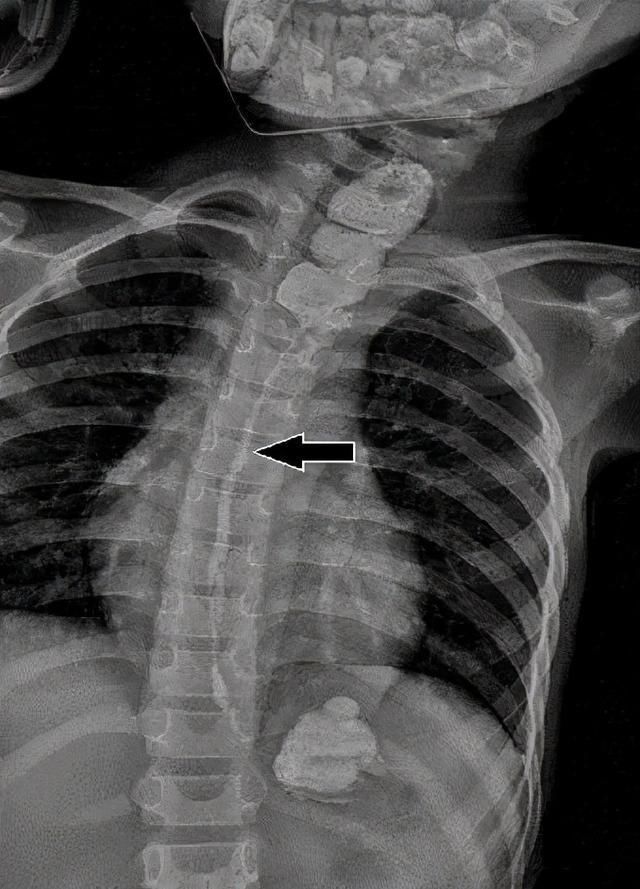

近日,小丽一家人找到了广东省妇幼保健院胸外科主任洪淳团队治疗,经过检查发现,小丽因误食了空调清洁剂后,造成了食管化学腐蚀后的狭窄,医生先给她尝试了无创的球囊扩张术,但因腐蚀后狭窄的时间较长,错过了保守治疗的最佳时机,球囊扩张并没有取得预期的效果,那么就只能考虑手术治疗了。术前的消化道造影显示:小丽食管中下段2/3严重狭窄,已经基本无法使用了!

术前造影食管狭窄